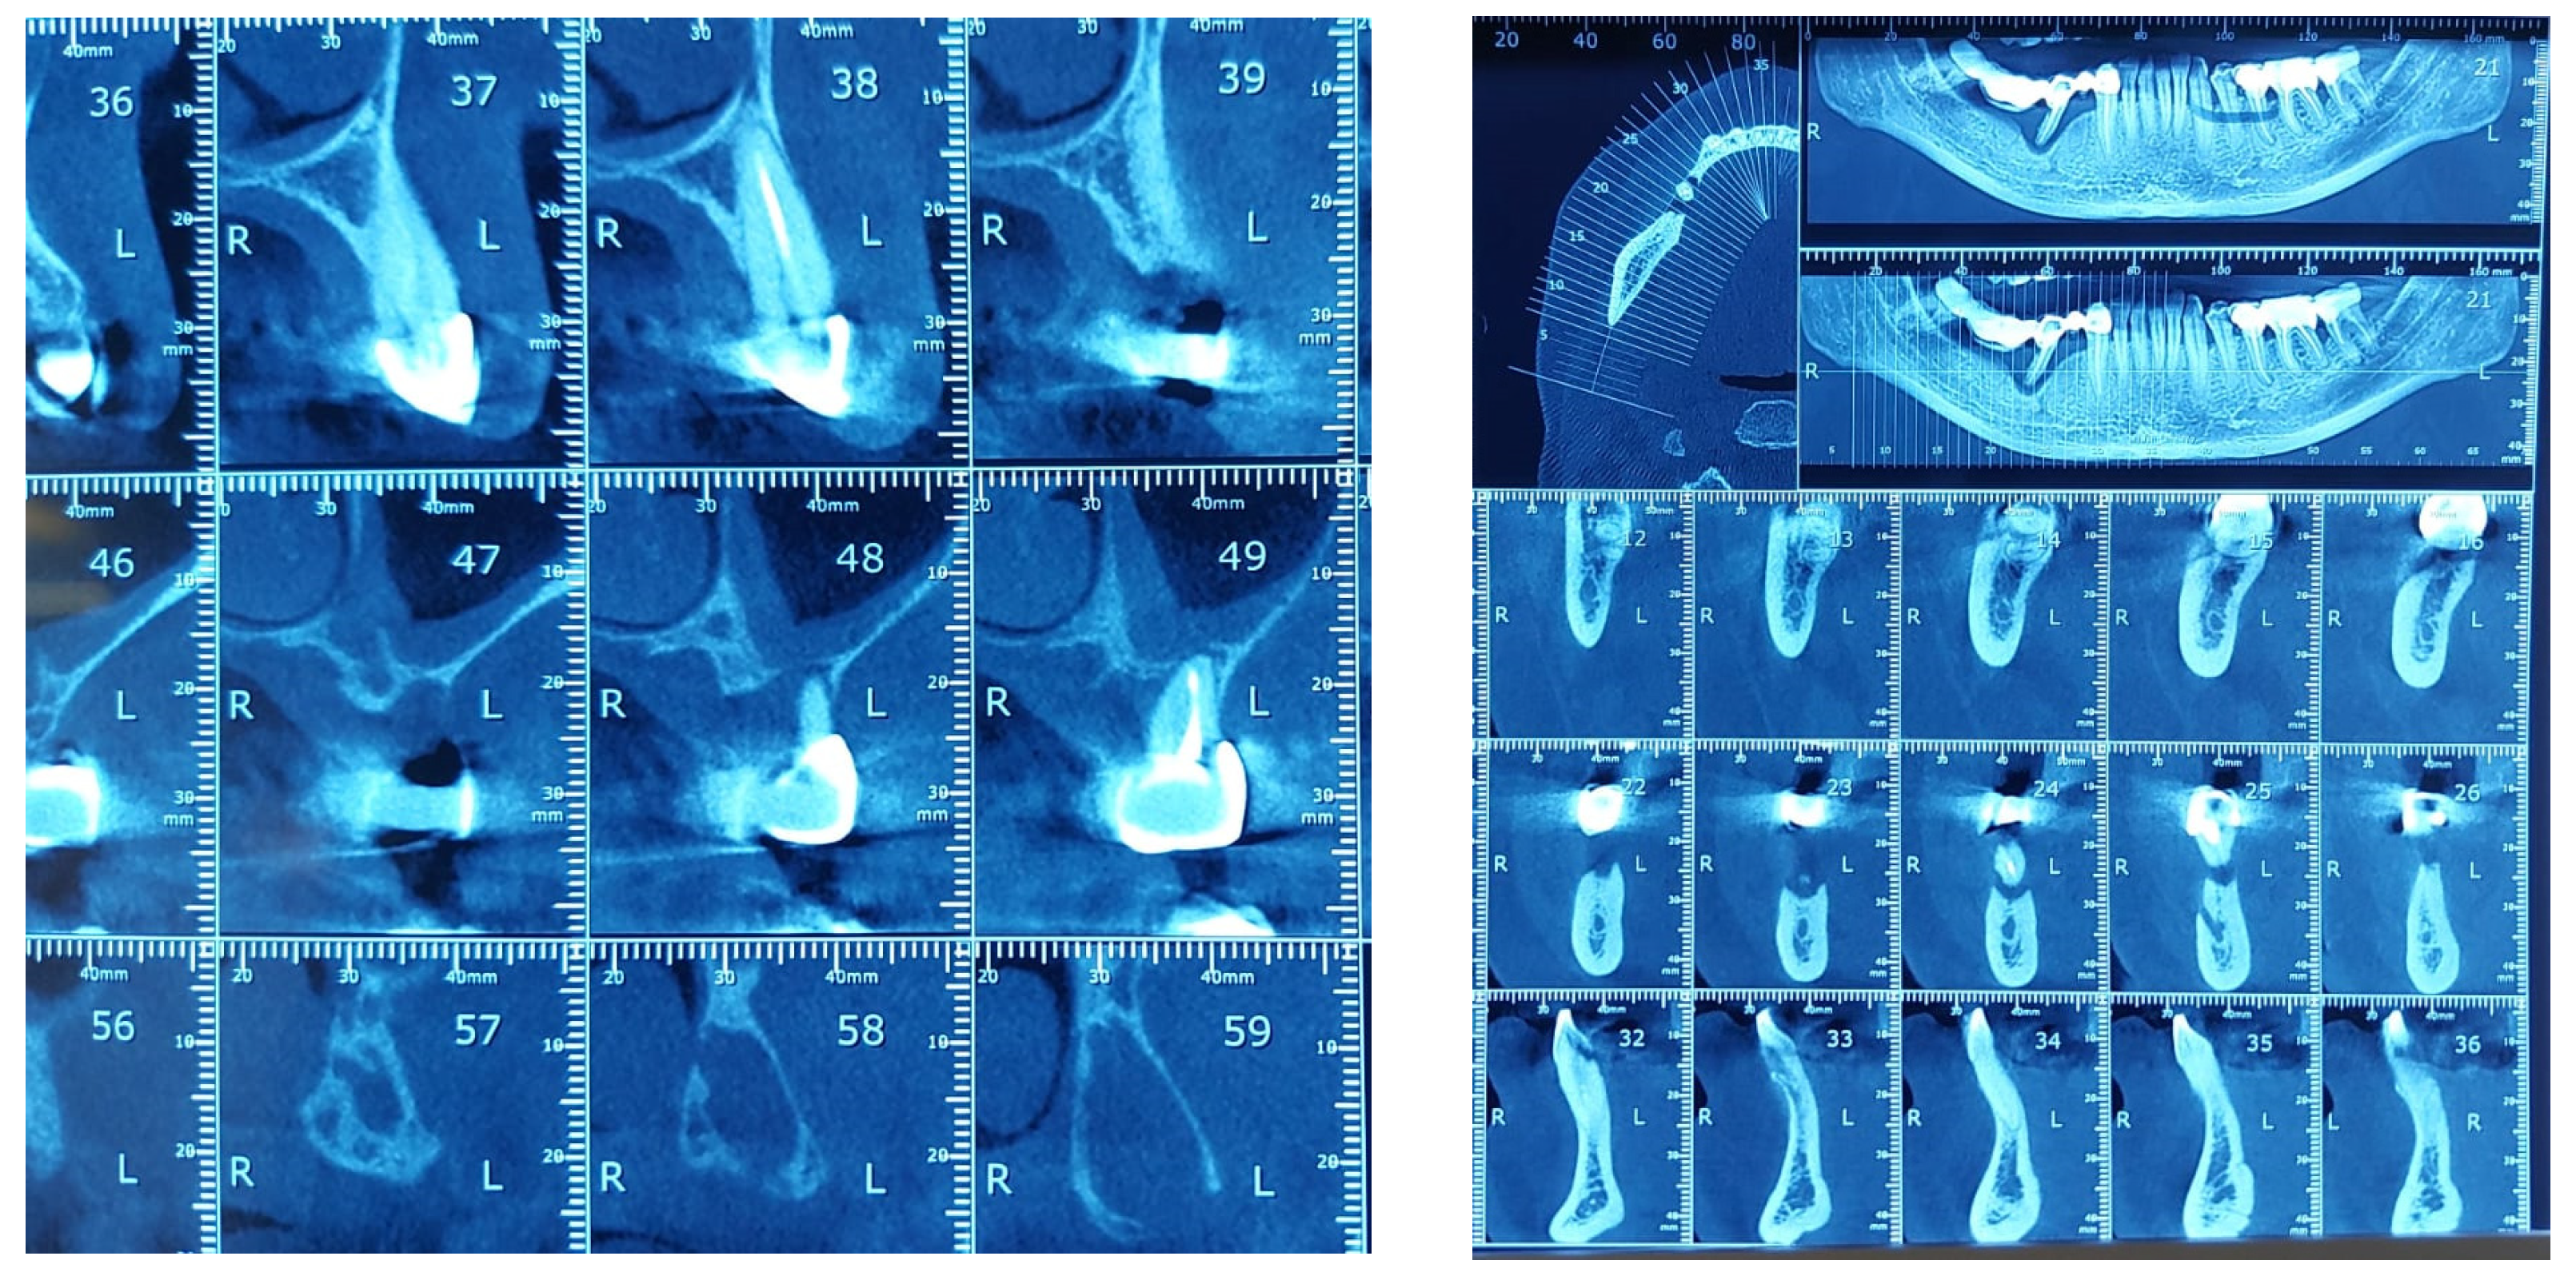

3. Materials and Methods